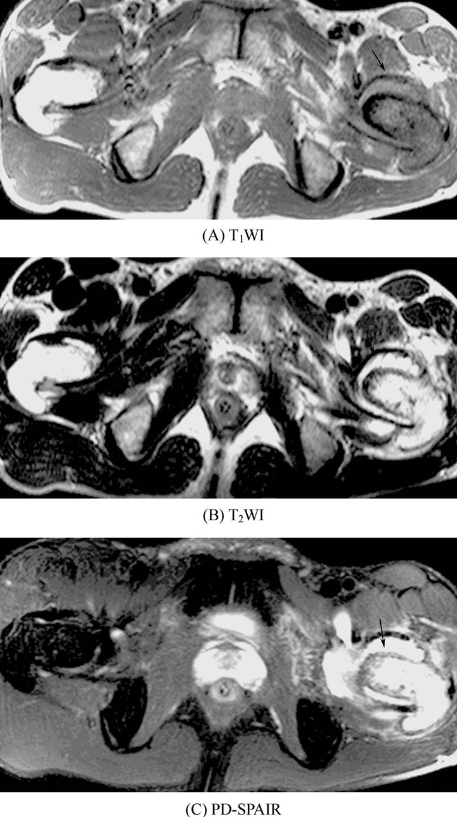

按肿瘤的发生部位,可分为中心型和周围型,前者发生于髓腔,呈中心性生长,后者发生于骨表面。MRI上可见软骨肉瘤于T1WI上表现为等信号或低信号,恶性度高的信号强度常更低;T2WI上,低度恶性的肿瘤因含透明软骨而呈均匀的高信号(图6),高度恶性的信号强度不均匀。钙化和骨化均呈低信号。中心型软骨肉瘤邻近骨皮质可有不同程度的膨胀、变薄,骨皮质或骨性包壳可被破坏而形成大小不等的软组织肿块。偶可见骨膜反应和Codman三角。周围型软骨肉瘤多为骨软骨瘤恶变而来,多表现为软骨帽不规则增厚变大,并形成不规则软组织肿块,原来的骨性基底可被破坏,甚至消失,增强扫描病变呈明显不均匀强化。

图6 软骨肉瘤左侧股骨近端增粗,内呈长T1、长T2信号,并见斑点状低信号影,PD-SPAIR呈明显高信号,骨皮质局部模糊不清,周围软组织内可见片状T2WI高信号影,左髋关节腔内见长T1、长T2信号影。